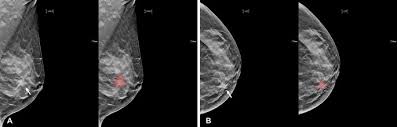

What Does Cancer Look Like On Mammogram : Mammography 3d Mammography Tomosynthesis Densebreast Info Inc / The rate of breast cancers discovered as dcis is thought to be increasing, but this is partially a testament to the effectiveness of mammographic breast cancer screening programs.ductal carcinoma in situ represents up to 30% of all new cases of breast cancer discovered by breast cancer screening.. Regular mammograms are the best tests doctors have to find breast cancer early, sometimes up to three years before it can be felt. In this mammogram image, the breast calcifications are in ductal patterns. Any area that does not look like normal tissue is a possible cause for concern. Calcifications are tiny flecks of calcium — like grains of salt — in the soft tissue of the breast that can sometimes indicate the presence of an early breast cancer. Any area that does not look like normal tissue is a possible cause for concern.

Abnormalities such as cancerous tumors usually appear brighter because they are denser. In this mammogram image, the breast calcifications are in ductal patterns. Dr sarah jarvis mbeif a mammogram is abnormal, further tests will be needed. Breast cancer and some noncancerous (benign) breast conditions can appear white on a mammogram. You may notice dimpling or pitting, and the skin on your breast.

X Ray Mammogram Showing Evidence Of Breast Cancer Stock Image M122 0050 Science Photo Library from media.sciencephoto.com But it's not uncommon that they see something that looks like it might be cancer —a finding that could end up being completely normal, but that needs to be further tested to be sure. What does cancer look like on a mammogram? The tumor cells don't stay within the clear borders of the mass, but instead invade the nearby breast tissue. This type of cancer also changes the appearance of your breasts. This can make it harder for your radiologist to spot signs of breast cancer, since dense tissue and tumors both look white in mammogram images. The look of breast cancer on a mammogram a tumor or lump will appear as a focused white area on the mammogram. A mammogram can show breast changes such as calcifications, masses, or other symptoms that might be cancer. Dr sarah jarvis mbeif a mammogram is abnormal, further tests will be needed.

Invasive breast cancer can appear as a white patch or mass on a mammogram. The tumor cells don't stay within the clear borders of the mass, but instead invade the nearby breast tissue. You may notice dimpling or pitting, and the skin on your breast. A rash isn't the only visual symptom of inflammatory breast cancer. Regular mammograms are the best tests doctors have to find breast cancer early. In a normal breast, a mammogram shows normal skin dark grey fat and lighter grey breast tissue. According to the american cancer society (acs), the most common sign of breast cancer is a new lump or mass in the breast. How can mammograms be used? Cancers may be seen as masses (like a ball, but usually with an irregular shape), areas of asymmetry that resemble normal tissue, calcifications (white specks), and/or areas of architectural distortion (imagine the puckering caused by pulling a thread in a piece of fabric). In this mammogram image, the breast calcifications are in ductal patterns. Healthy mammograms can still vary in appearance. It is important to bear in mind that most women who are asked to come back after. Any area that does not look like normal tissue is a possible cause for concern.

Ibc symptoms are caused by cancer cells blocking lymph vessels in the skin causing the breast to look inflamed. symptoms include breast swelling, purple or red color of the skin, and dimpling or thickening of the skin of the breast so that it may look and feel like an orange peel. What does cancer look like on a mammogram? Cancers may be seen as masses (like a ball, but usually with an irregular shape), areas of asymmetry that resemble normal tissue, calcifications (white specks), and/or areas of architectural distortion (imagine the puckering caused by pulling a thread in a piece of fabric). Tumors may be benign or cancerous. According to the american cancer society (acs), the most common sign of breast cancer is a new lump or mass in the breast. Suspicious findings include clusters of tiny microcalcifications or a density/mass with irregular or spiculated margins. Any area that does not look like normal tissue is a possible cause for concern. This can make it harder for your radiologist to spot signs of breast cancer, since dense tissue and tumors both look white in mammogram images. Breast cancer and some noncancerous (benign) breast conditions can appear white on a mammogram. This is considered an abnormal mammogram, but not necessarily one that's indicative of cancer. Invasive breast cancer can appear as a white patch or mass on a mammogram. By the time it's diagnosed, it usually has grown into the skin of your breast. What does an abnormal mammogram look like?